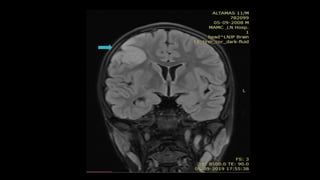

CROSSED CEREBELLAR DIASCHSIS

• #97 this is an example showing Diffusion w and TTP perfusion images showing acute ischemic lesion in left thalamus with hypoperfusion in the corresponding location . In the cerebellum ,trace dwi is unremarkable while TTP demonstrate hypoperfusion in contralateral cerebellar hemisphere